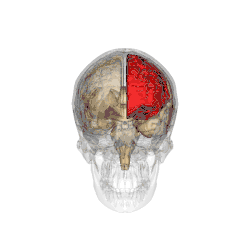

Functional magnetic resonance imaging (fMRI) scans of the brains of subjects exposed to thirty-five hours of sleep deprivation indicate that sleep deprivation is related to increases in prefrontal cortex and parietal lobe activation during tasks that combine verbal learning and arithmetic. This is particularly apparent in the right hemisphere. In non-sleep-deprived people involved in verbal learning and arithmetic tasks, the anterior cingulate cortex and the right prefrontal cortex are active. Following sleep deprivation, there is increased activation of the left inferior frontal gyrus and the bilateral parietal lobes. This information suggests that divided attention tasks require more attentional resources than normally required by a non-sleep-deprived person.[5]

Deficits in cognitive performance due to continuous sleep restriction are not well understood. Studies have looked into physiological arousal of the sleep-deprived brain. Participants, whose total amount of sleep had been restricted by 33% throughout one week, were subjected to reaction time tests. The results of these tests were analyzed using quantitative EEG analysis. The results indicate that the frontal regions of the brain are first to be affected, whereas the parietal regions remain active until the effects of sleep deprivation become more severe, which occurred near the end of the week. EEG and ERP analysis reveals that activation deficits are more apparent in the non-dominant hemisphere—than in the dominant hemisphere.[11]

By contrast, other studies have indicated that the effects of sleep deprivation on cognitive performance, specifically sustained visual attention, are more global and bilateral in nature (as opposed to more lateralized deficit explanations). In a study using the Choice Visual Perception Task, subjects were exposed to stimuli appearing in various locations in visual space. Results indicate that sleep deprivation results in a general decline in visual attention. It is also suggested that the sleep-deprived brain is able to maintain a certain level of cognitive performance during tasks requiring divided attention—by recruiting additional cortical regions that are not normally used for such tasks.[14]

Lack of sleep changes how genes are expressed and interferes with neurobiological functions that are necessary for cognitive function. Research indicates a decline in the expression of proteins that are essential for memory consolidation and synaptic plasticity, including CREB and PKCγ. These molecular abnormalities damage the cerebellum and hippocampus, which results in deficiencies in long-term memory functions and spatial working memory. Chronic sleep deprivation also raises the brain's amyloid-beta aggregation, which is linked to neurodegenerative diseases like Alzheimer's. Impaired clearance mechanisms during reduced sleep worsen this neurotoxic environment. Neuroimaging studies also show a shift of cognitive resources, which decreases activation in the prefrontal cortex and parietal lobes and increases activation in areas like the thalamus. However, this compensating strategy is not enough to sustain the best possible cognitive function throughout extended periods of wakefulness.[61][62]